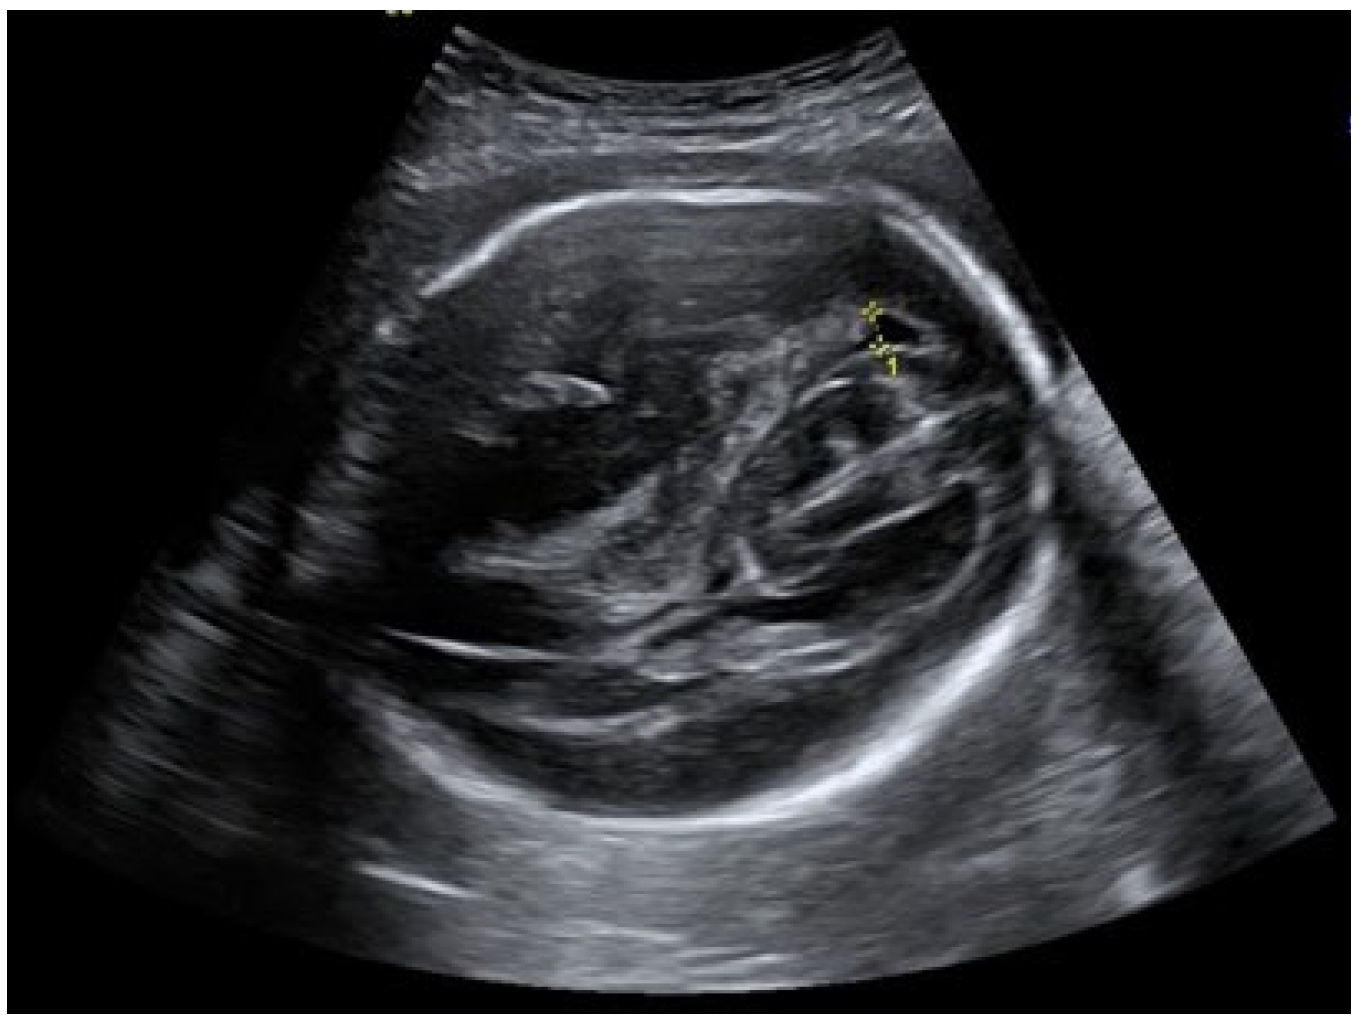

An ultrasound examination of the fetus was carried out through the abdominal wall, during which, pathological changes in the fetal brain were first observed (Figure 1, Figure 2 and Figure 3). A suspected tumor-like mass (2.75 × 2.16 cm) was seen in the anterior cerebral lobe of the right hemisphere, and dislocation of middle line and mild ventriculomegaly (1.38 cm) of the left lateral ventricle of the brain was present. Magnetic resonance imaging (MRI) of the fetal brain was carried out to establish the diagnosis (Figure 4).

Figure 2.

Right lateral ventricle and dislocated middle line of fetal brain.

Figure 3.

Ventriculomegaly of the left lateral ventricle.